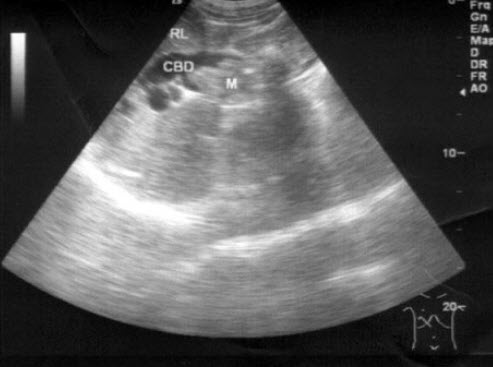

11、单项选择题

患者女47岁,皮肤、巩膜黄染,进行性加重2个月余,腹痛、腹胀,既往有胆结石病史。B超检查如图所示,根据超声声像图,诊断为()

A.胆总管癌并结石

B.胆总管胆泥淤积

C.胆总管结石

D.胆总管蛔虫

E.胆总管癌